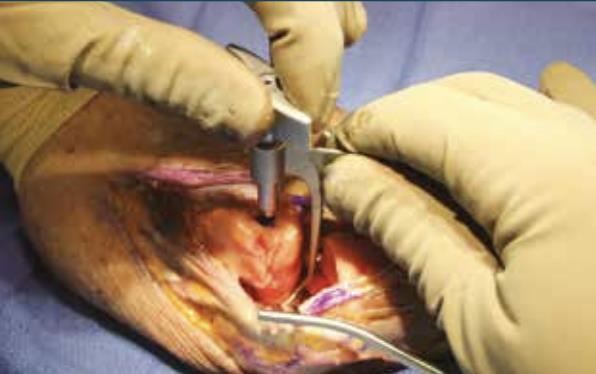

• Base plate positioning

• position the Base Plate on the proximal aspect of the ulna

• Base plate drilling

• drill for bicortical fixation through the sliding slot on the Base Plate using the 2.7mm drill bit, aiming towards the coronoid process and away from the radial notch

• measure using the Depth Gauge for the appropriate length 3.5mm compression screw (Polyaxial Non Locking)

• Axis pin measurement

• insert the corresponding 3.5mm compression screw (Polyaxial Non Locking) using the T-10 Driver

• repeat past two steps for the remaining two compression screw holes of the Base Plate